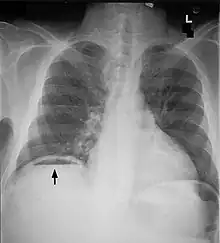

| Frontal chest X-ray. The air bubble below the right hemidiaphragm (on the left of the image) is a pneumoperitoneum. | |

Pneumoperitoneum is pneumatosis (abnormal presence of air or other gas) in the peritoneal cavity, a potential space within the abdominal cavity. The most common cause is a perforated abdominal organ, generally from a perforated peptic ulcer, although any part of the bowel may perforate from a benign ulcer, tumor or abdominal trauma. A perforated appendix rarely causes a pneumoperitoneum.

When present, pneumoperitoneum can be seen on projectional radiography, but small amounts are often missed, and CT scan is nowadays regarded as a criterion standard in the assessment of a pneumoperitoneum.[18] CT can visualize quantities as small as 5 cm3 of air or gas.

Signs that can be seen on projectional radiography are shown below: